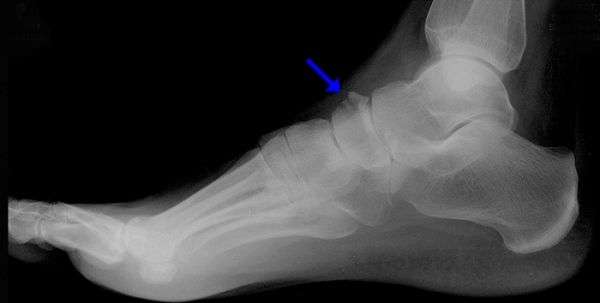

На самом деле все было очень серьезно. Потенциальная звезда кортов NBA получила диагноз - ПЕРЕЛОМ ЛАДЬЕВИДНОЙ КОСТИ (такая же травма поставила точку на карьере Яо Мина). Ладьевидная кость – это маленькая косточка в нашей ступне, которая отвечает за правильное распределение веса тела на стопу во время движении. Учитывая рост и вес Джордана, игра с такой травмой была просто невозможна. Произошедшее стало большим ударом для команды «Быков». В прошлом сезоне только благодаря новичку они пробились в плей-офф, а теперь он вне игры. Также своей травмой Майкл подставил и Nike, компания очень сильно рисковала, когда заключала дорогостоящий спонсорский контракт.